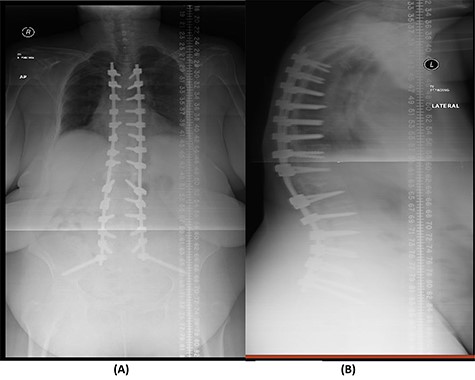

The bridging technique was used to achieve relative stability through posterior fixation until the anti-TB medications cleared the vertebral infection and allowed re-ossification of the destructed levels (T11–L3) to occur. An open biopsy was done intraoperatively to reconfirm the diagnosis of spinal TB. The patient started mobilizing early postoperatively and continued to take the anti-TB medications for 18 months (Fig. 4).

(A) AP lumbar spine X-ray demonstrating the bridging technique. (B) Lateral spine X-ray showing the bridging technique sparing the infected area.

The success rate of surgical TB management is high and effective according to a study based on data collected from 582 patients throughout 11 years [8]. Our patient presented with a destructive spinal lesion and underwent posterior spinal decompression and instrumentation of T11–L3. Nevertheless, due to severe destruction, loosening and poor bone quality of the levels T11–L3, along with the multiple medical comorbidities, anterior surgical intervention with a thoracoabdominal approach with resection of all the levels involved would associate with major morbidities and complications. To achieve a balanced construct and to have multiple fixation points, which was needed to overcome the poor bone quality, the fixation was done from T5 down to the pelvis (Fig. 4), spanning the destructed area and utilizing the bridging technique with multiple rod constructs across the T11–L3 region.